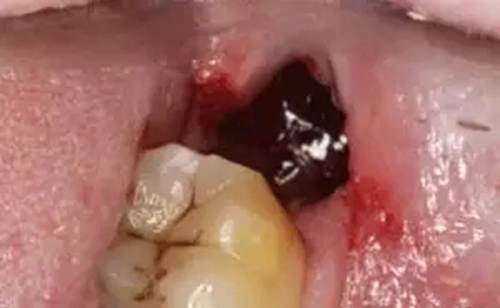

目前認為干槽癥是智齒拔除術后發(fā)生在拔牙窩局部的局限性骨炎。正常的拔牙窩愈合是牙齒拔出術后,血塊充滿拔牙窩后形成了高質量的充填物,凝固后保護拔牙窩,促進傷口的愈合。而在愈合過程中,如果凝血塊脫落或者感染,就可能會導致干槽癥。

正常拔牙窩會有血凝塊保護

拔牙干槽癥可怕嗎?

口腔照